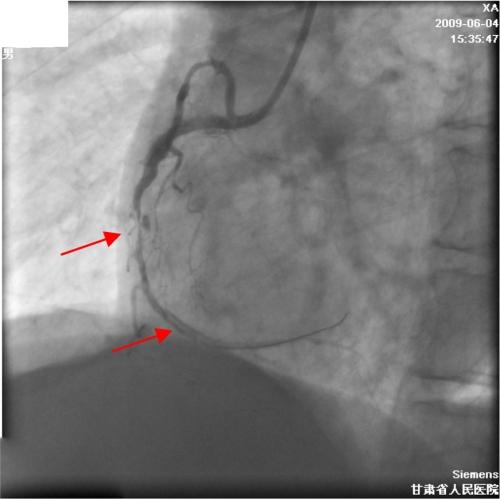

右冠状动脉经皮介入治疗期间对瓦氏窦冠状窦的广泛解剖——病例报告及文献综述

Extensive dissection to the coronary sinus of valsalva during percutaneous intervention in right coronary artery-a case report and literature review.

Severe retrograde dissection extending into the sinus of Valsalva is a rare complication during percutaneous coronary intervention (PCI), but life threatening. There is some literature about this complication, but this particular complication has not been previously reported in China. We present a case of coronary artery dissection during a PCI in which progressively extended retrogradely into the sinus of valsalva, and was successfully treated with stenting without an operation.

摘要

严重的逆行性夹层扩展至主动脉瓣窦是经皮冠状动脉介入治疗(PCI)期间罕见但危及生命的并发症。关于这一并发症有一些文献报道,但在中国此前尚未报道过这种特殊的并发症。我们报告一例PCI期间冠状动脉夹层病例,该夹层逐渐逆行扩展至主动脉瓣窦,并成功通过支架置入治疗,未进行手术。